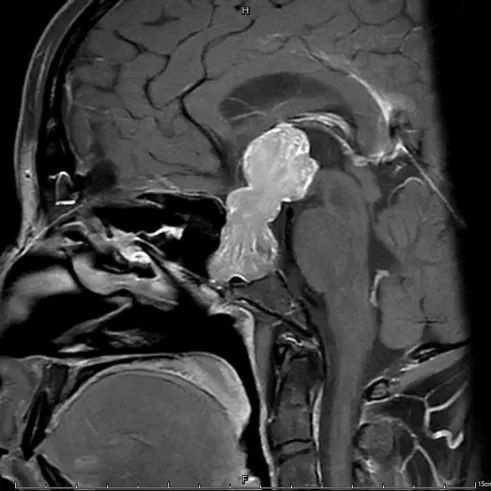

黄女士是在一次例行体检中发现这颗巨大的脑部肿瘤的。平时忙于拼事业,不时发生的头痛在她看来并非什么不得了的症状,然而当体检影像报告呈现在眼前时,她惊呆了:横在大脑中间的一个巨大肿瘤,就像座铁搭一样,竖立在鞍区,即大脑的中心位置,形状酷似葫芦,最大径达到6cm,向下侵犯斜坡和蝶窦,向上在视交叉后方顶起了下丘脑,突入到第三脑室抵达孟氏孔。

这个肿瘤堪称罕见,它占到了成人大脑的1/20左右,相当于在一个10平米见方的小卧室中央,放了一只高达1米的大葫芦。肿瘤如果不及时处理,后续可能会造成脑积水,智力下降、行走困难;视力下降,视野缺损直至失明;月经周期延长或停经;眼球活动障碍、面部感觉减退等等多方面问题。

黄女士术前(左)术后(右)影像对比